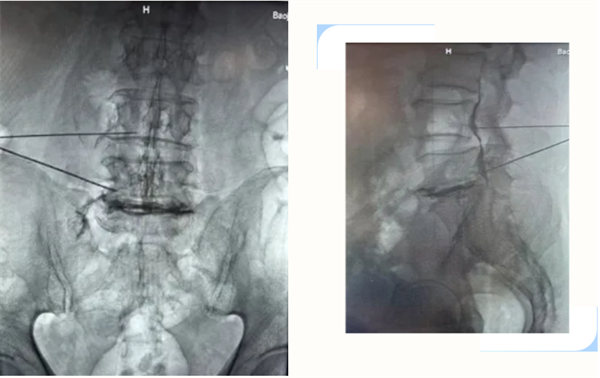

55歲的何師傅,反復(fù)腰背部疼痛不適,曾多次行保守治療,效果不理想,近3月來癥狀逐漸加重,伴有左臀部、左大腿疼痛,行走困難,遂就診我院骨四科,患者對常規(guī)手術(shù)非??謶帧H朐汉螅浦魅螚钣垒x及團(tuán)隊(duì)結(jié)合患者一般情況、癥狀、查體及影像學(xué)檢查,診斷為:腰椎間盤突出癥(L5-S1),綜合評估病情后,考慮到患者的訴求。為患者行L5-S1椎間盤突出膠原酶化學(xué)溶解+臭氧術(shù)。該技術(shù)無需開刀,僅需透視下“注射一針”,化學(xué)溶解突出、脫出的髓核,術(shù)后患者癥狀較前明顯好轉(zhuǎn),可佩戴腰部固定支具下床活動(dòng)。為同類患者提供新的選擇。

指將膠原酶及臭氧在C型臂引導(dǎo)下,精準(zhǔn)注射到突出椎間盤內(nèi)及周圍,一方面溶解并吸收突出椎間盤,另一方面抑制炎性因子滲出,促進(jìn)組織修復(fù),從而減輕神經(jīng)根壓迫及炎性刺激,達(dá)到緩解疼痛、改善癥狀、提高生活質(zhì)量的效果。